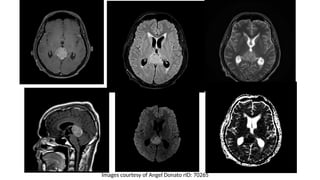

CT Findings

• High cellular tumor

• Slight hyperdense mass, somehow lobulated

• Avidly enhancing post contrast

• Characteristically “engulfs” the pineal gland and promotes its

calcification, resulting in a central of calcification.

MRI findings

• T1W and T2W:Iso-hyperintense

If cystic necrotic foci (High SI TW2)

• FLAIR: Slightly hyperintense

• DWI/ ADC: Restriction diffusion

• T1W+C: Strong homogenous enhancement

Images courtesy of Angel Donato rID: 70265

• #17 A large lobulated mass is centered on the pineal gland, engulfing the pineal calcifiation. It is somewhat hyperdense compared to adjacent brain. A further smaller mass is seen in the floor of the third ventricle. The midbrain is distorted, compressed and demonstrates low density suggestive of edema. Obstructive hydrocephalus is present.  Pineal germinoma with a synchronous suprasellar germ cell tumor

• #18 T1W fat sat + C FLAIR T2W T1W C+ Sag DWI ADC There is a large pineal region mass with moderate enhancement with compression of the tectum resulting in obstructive hydrocephalus. On SWAN imaging the pineal calcification is confirmed to be placed centrally. On T2 the pineal mass is hyperintense. Diffusion-weighted imaging (DWI) shows restriction with low apparent diffusion coefficient (ADC) values.